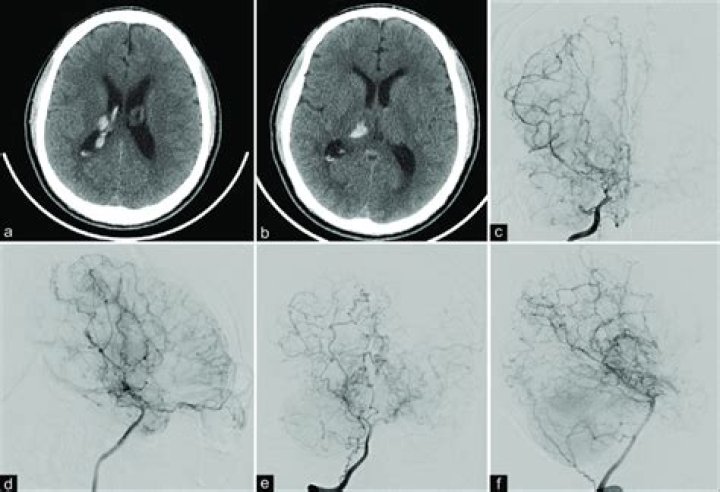

Is thalamic hemorrhage intracerebral?

Thalamic hemorrhage is the second most common location of nontraumatic intracerebral hemorrhage, accounting for 10% to 15% of all hemorrhages. The clinical picture depends entirely on hematoma size, selective or global involvement of the different thalamic nuclei, and the involvement of neighboring structures.

Hypertension is the most common cause of thalamic hemorrhage. During the first month following thalamic hemorrhage, mortality is about one in ten among those whose hemorrhage is restricted to the thalamus, but increases to one-third if the hemorrhage also involves the ventricles.